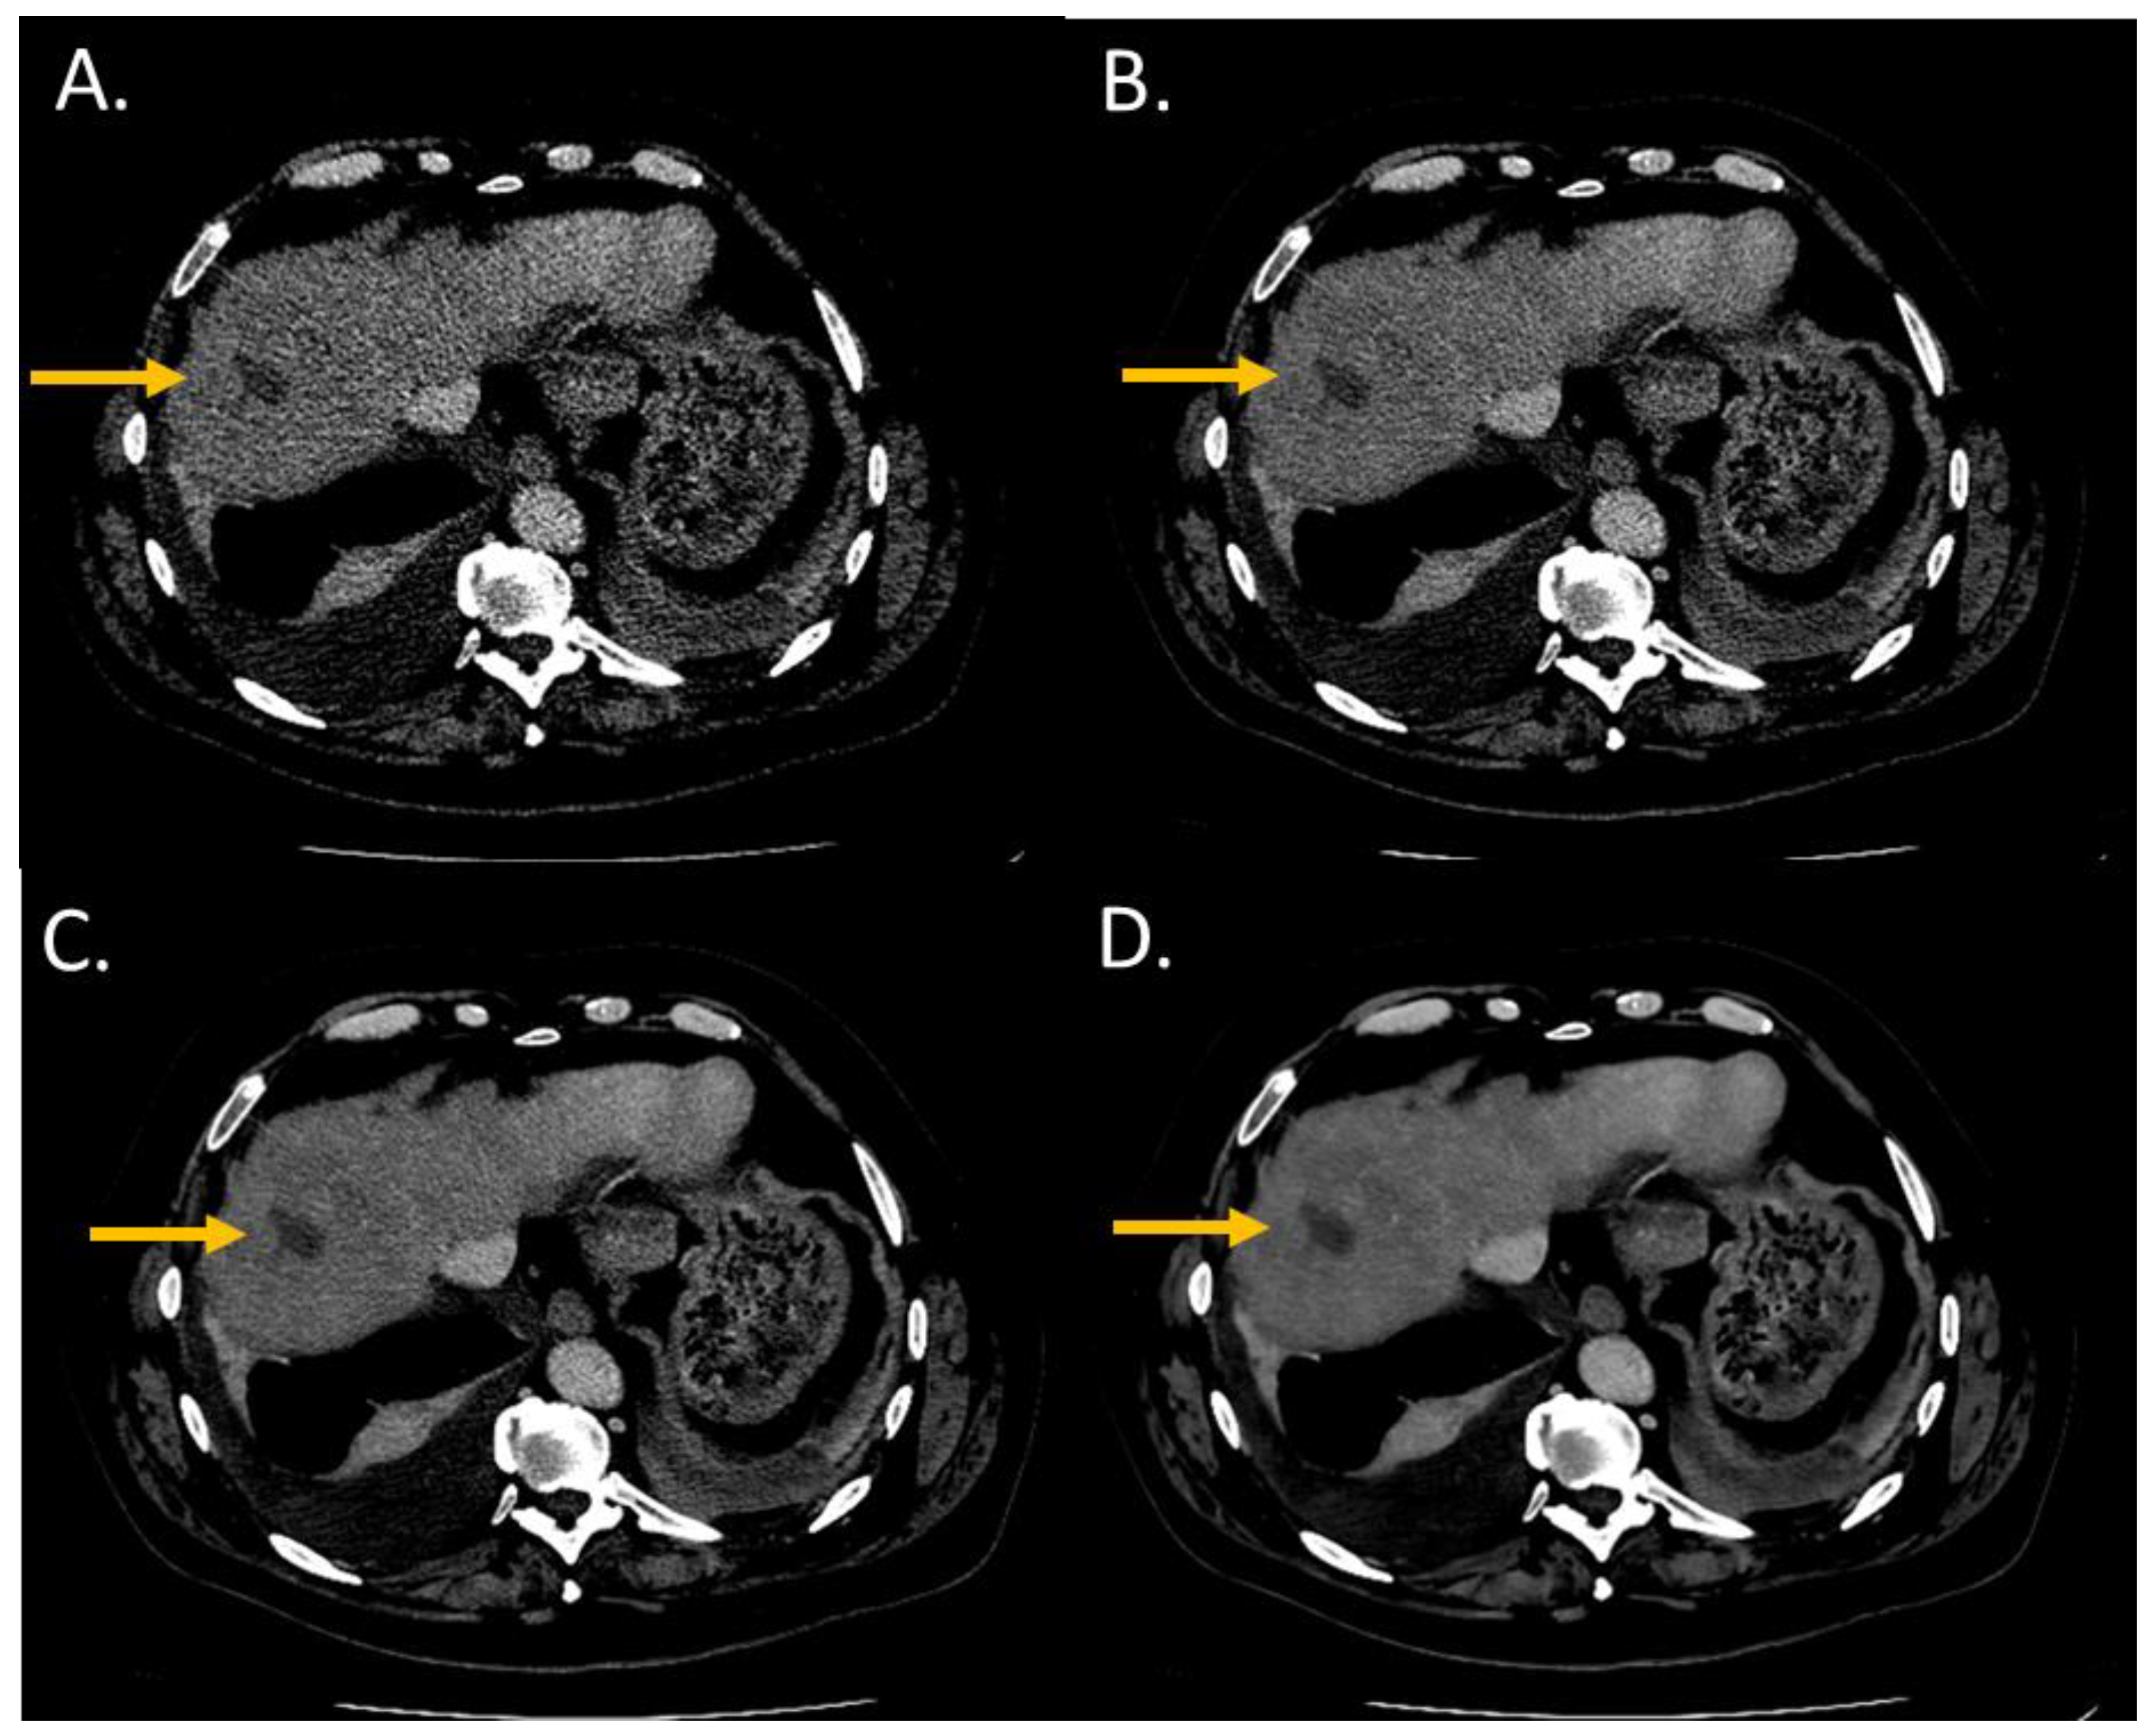

The overall image quality score significantly increased from i4 to the Standard level (p < 0.05) and from the Standard to the Smoother level (p < 0.05) (Figure 1). Both radiologists rated the overall image quality as “Interpretable despite moderate artefacts or noise” for all patients with i4. For all DLR levels, the overall image quality was rated as “Fully interpretable with mild artefacts or noise” or as “No artefacts or noise”. Agreement between the two radiologists was “excellent” for the Standard and Smooth levels. For i4 and the Smoother level, the two radiologists rated the images with the same score for all patients.

Figure 1.

Overall image quality of abdominal CT images (WL: 60 HU; WW: 360 HU) of a woman with pancreatic cancer and abdominal metastatic lesions (63 years old; SSDE: 9.09 mGy; average scan size 32.2 cm). (A) iDose4 level 4; average overall image quality score: 2.5; (B) Precise Image, Standard; average overall image quality score: 3; (C) Precise Image, Smooth; average overall image quality score: 4; (D) Precise Image, Smoother; average overall image quality score: 4.